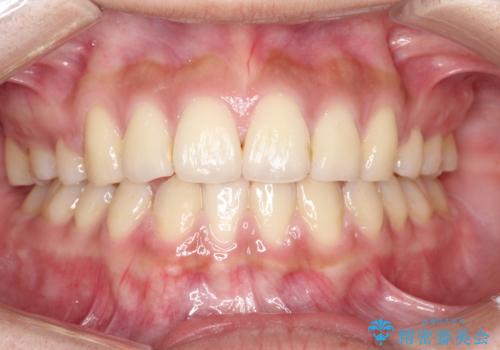

横顔をすっきりさせたい 下の前歯が1本少ない方の変則的な抜歯矯正

- 口元を引っ込めたいとのことで来院されました。

口元の突出感がありと、下顎の前歯が1本欠損していました。

上顎の前から両側の前から4番目の歯と、下あごの前歯を1本抜歯して、口元をすっきりさせる計画としました。